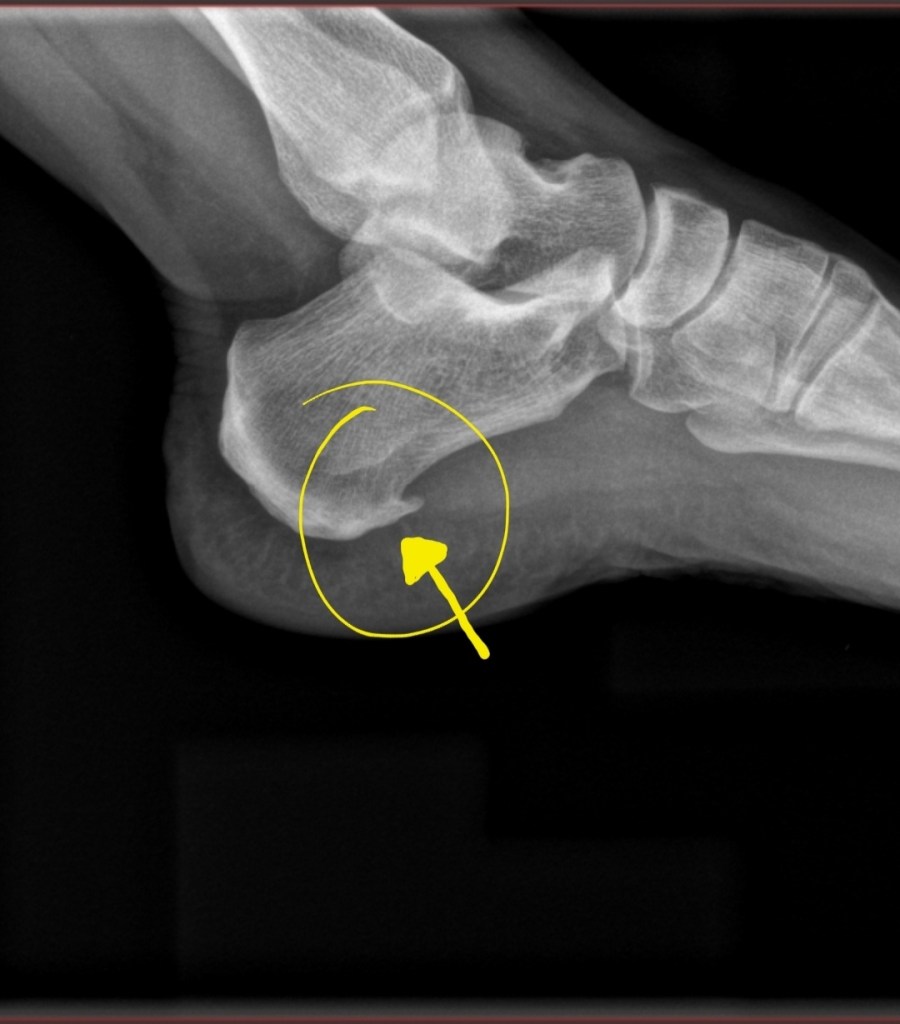

In those X-rays, we can see a bone spur on my left foot heel – a calcaneal heel spur – that has been causing me pain when I put pressure on my heel. This can stem from Plantar Fasciitis – degeneration of the band of tissue (fascia) at the bottom of your feet that runs from your heel to your toes.